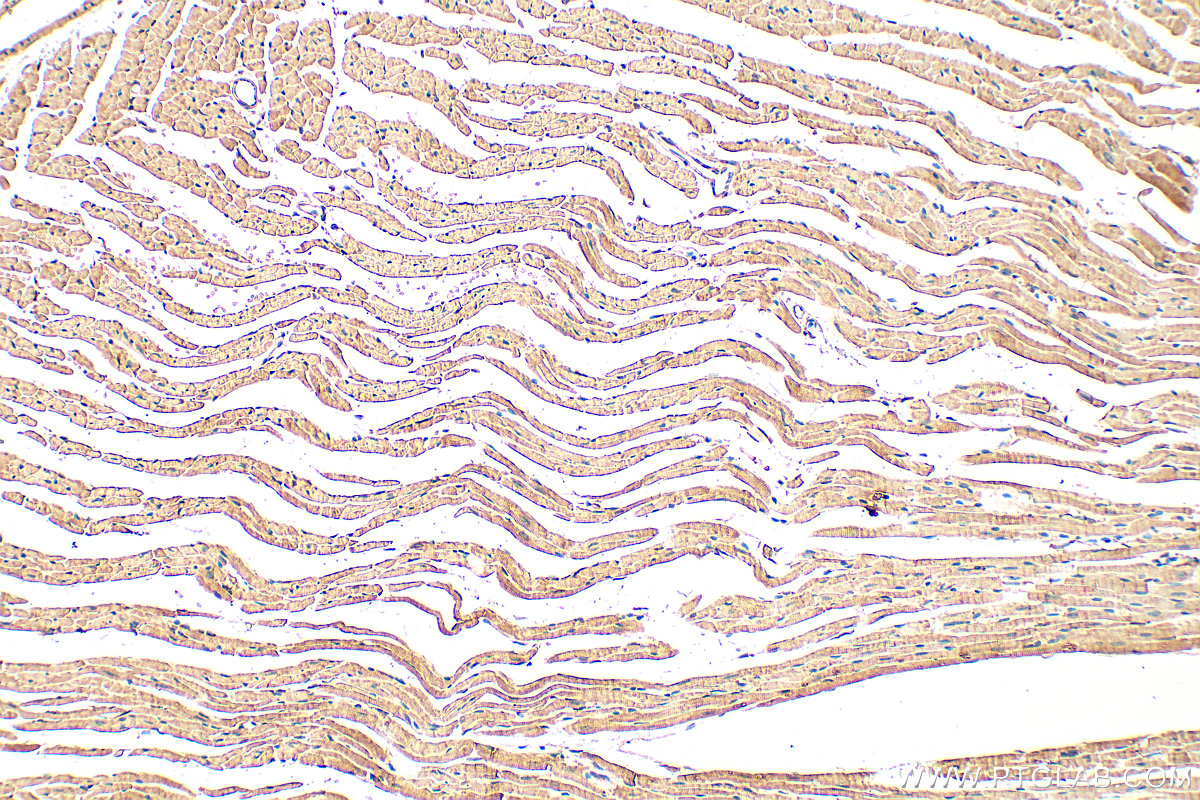

| Positive IHC detected in | mouse heart tissue, human heart tissue, human skeletal muscle tissue, mouse skeletal muscle tissue Note: suggested antigen retrieval with TE buffer pH 9.0; (*) Alternatively, antigen retrieval may be performed with citrate buffer pH 6.0 |

| Immunohistochemistry (IHC) | IHC : 1:50-1:500 |